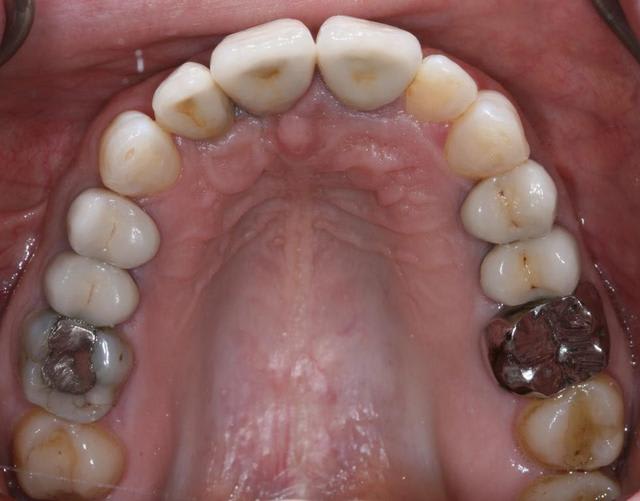

Bon ben j'ai implanté avant d'avoir refait la 21. Du coup j'ai mésialé la pose de 11 pour compenser la distalisation de 21.

Au final je n'ai pas fait de greffe osseuse... et j'ai réalisé une technique de rouleau sur 11-12 mais je reste un peu court à mon goût.

J'ai mis en place des transitoires sur 11-12-21 pour temporiser 3 mois pour voir la maturation des tissus mous.

Je réaliserai dans un second temps des piliers procera.

Je mets quelques photos de la patiente au cab et du prothèsiste d'Epinal.

La vraie difficulté a été de retrouver le milieu incisif pour déterminer la position des implants.

Les provisoires sont solidaires ? ( bravo pour le parallélisme)

Le zénith de la 21 doit être un peu plus distal pour que le résultat soit plus sympa

(comme tu l'as si bien fit sur la 11, allez quoi, un petit coup de bistouri et hop tu gagnes en esthétique)